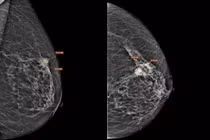

Cụ bà 75 tuổi bất ngờ khi phát hiện ung thư vú giai đoạn xâm nhập

Bệnh nhân cao tuổi mắc ung thư vú thể ống xâm nhập, được phát hiện nhờ xét nghiệm giải phẫu bệnh, mở ra cơ hội điều trị thành công.

Không ít người cho rằng ung thư vòng 1 chủ yếu xảy ra ở phụ nữ trung niên, trong khi tuổi cao được xem là giai đoạn ít rủi ro hơn. Thực tế lâm sàng cho thấy, quan niệm này tiềm ẩn nhiều nguy cơ, bởi ung thư vòng 1 có thể xuất hiện ở mọi độ tuổi.

Mới đây, bệnh nhân là bà N.A.T (75 tuổi) đến thăm khám tại Bệnh viện Đa khoa Medlatec trong tình trạng có khối u tại vú trái. Bà T. cho biết, bản thân chỉ nghĩ đơn giản đó là những thay đổi lão hóa tự nhiên của tuổi già.